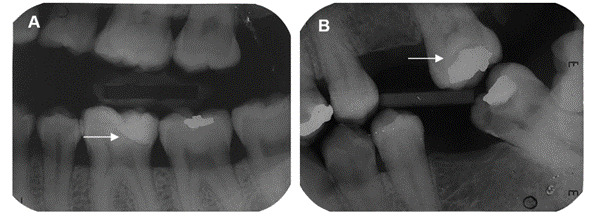

The combination of different methods has been advocated to increase sensitivity in detecting secondary caries lesions. This cross-sectional study compared the detection of caries lesions around posterior restorations and treatment decisions using bitewing radiographs alone or in combination with clinical information from patient records. The radiographs (n = 212) were randomly distributed into two sequences for assessment across two phases, with a wash-out period of two weeks. In the first phase (X-ray group), the radiographic images were evaluated without clinical information; in the second phase (X-ray/CARS group), the radiographic images were assessed in conjunction with the CARS score (Caries Associated with Restorations or Sealants) and lesion activity. A radiographic classification system for carious lesions around restorations was adapted to classify the bitewing radiographs included in this study. Evaluations were conducted in consensus by a panel of specialists, focusing on the detection of caries around restorations and subsequent treatment decisions. A chi-squared test was used to compare treatment decisions between the groups, and Cohen's kappa coefficient was employed to assess the agreement of scores. The results showed a significant difference in the distribution of decisions regarding the need for restorative intervention between the groups (p < 0.001), with the X-ray/CARS group leading to more decisions favoring restorative intervention. There was a moderate to good agreement of scores (κ = 0.749). The combination of clinical and radiographic information was found to influence the treatment decision-making process by increasing the likelihood of opting for restorative intervention.